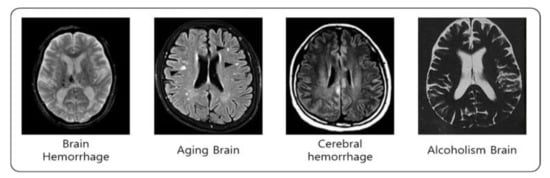

Table 2 shows that MMSE has the highest correlation. MMSE is the method that is the most widely used dementia screening test, which simply evaluates cognitive function and dementia in a short time. Thus, it is inferred that the factors affecting cognitive function may change the dementia condition. This conducts a test based on 30 points, and the questions consist of time and place orientation, registration, attention and calculation, memory recall, language, and visuospatial function. MMSE judges higher than 24 points as the normal range; 20–23 points as suspected dementia and cognitive dysfunction; and less than 19 points as a high likelihood of having dementia and cognitive dysfunction. Accordingly, this study recollected data concerning the factors affecting cognitive function. This is based on the information in the National Center for Mental Health [] and Dementia Center []. The recollected data are from an alcoholism brain, an aging brain, a brain with cerebral hemorrhage, and hemorrhage brain. Thus, the brain image data are collected from patients who have symptoms related to these. Figure 4 shows the recollected image data.

Figure 4.

Recollected image data.

In Figure 4, in the traumatic brain injury, the blood spreads and pools, and the aging brain is contracted (wrinkled) in the upper parts on the left and right. In addition, if there is cerebral hemorrhage, the brain expands, and the head is full. In the alcoholic brain, the brain is shrunken.